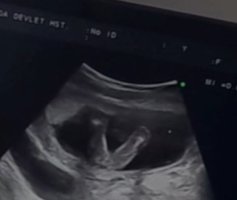

Elimde sadece bu görüntüler var dünden. Videodan alıntı yaptım ama kıza benziyor gibi doktor da emin olamıyor o yüzden ayrıntılıya kalacak.

• Screenshot_20230616-184925_Video Player.jpg

Screenshot_20230616-184925_Video Player.jpg

26,1 KB · Görüntüleme: 112